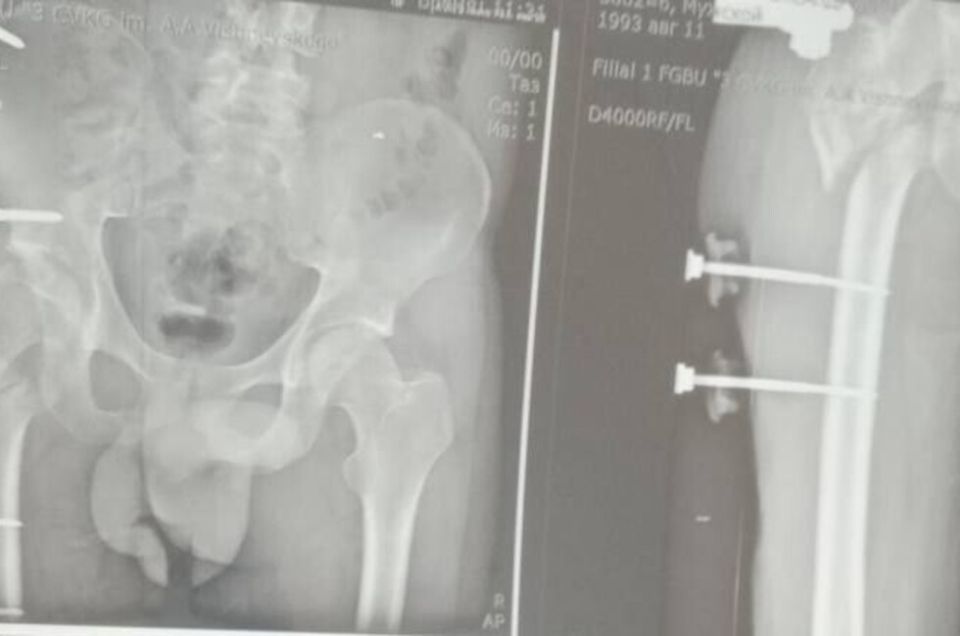

Донецк, 17 мар — ДАН. В Луганской республиканской клинической больнице провели уникальную операцию, которая вернула ветерану СВО возможность ходить без хромоты. Об этом сообщил ЛИЦ со ссылкой на министра здравоохранения ЛНР Наталию Пащенко. ...